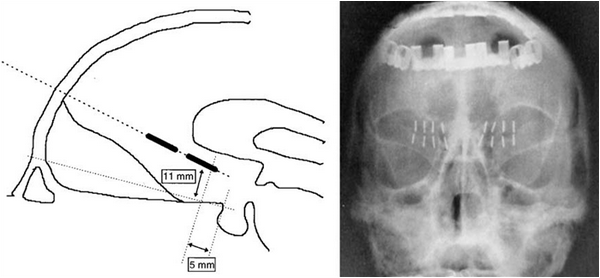

Стереотаксическая рамочная система, разработанная Шпигелем и Вайссом в 1947 г.

Стереотаксическая нейрохирургия вдет свою историю с аппаратов Д. Н. Зернова и Горслея - Кларка, созданных на рубеже 19-20 столетий, однако только вариант стереотаксической системы Ричардсона-Вайсса (1947 г.) натолкнул различных исследователей на мысль о применении ее для деструкции весьма небольших структур круга Пейпеца [1,2].

В 1961 г. Джеффри Найт предлагает устанавливать стереотаксически 3-5 иттриевых стержней 1х7 мм билатерально в белом веществе впереди и ниже головки хвостатого ядра для лечения тревожных и депрессивных расстройств и ОКР, процедура была названа им субкаудатная трактотомия.

Разработка Джефри Найта